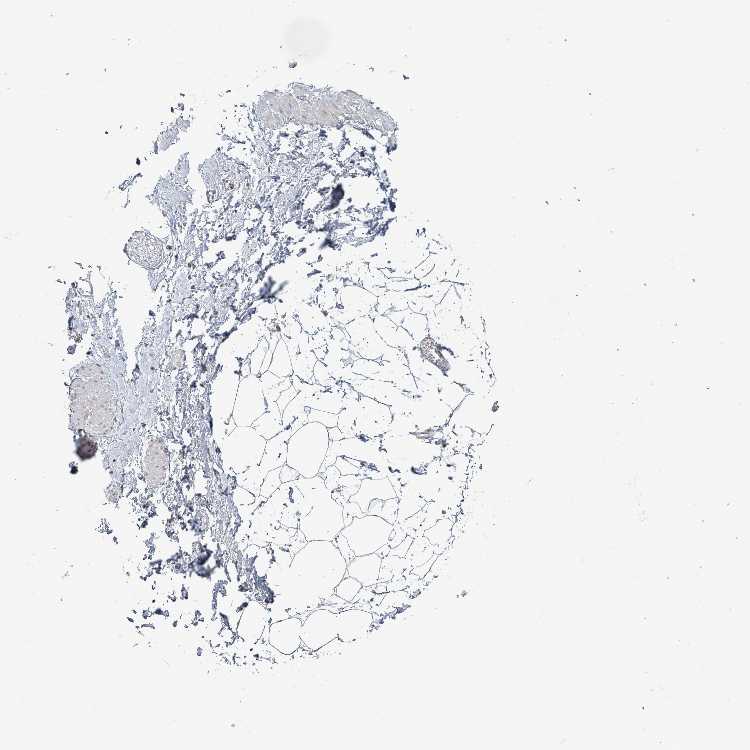

TISSUE PRIMARY DATA SOFT TISSUE Show tissue menu

SOFT TISSUE - Expression summary

SOFT TISSUE 2 - Antibody stainingi

Antibody staining in the annotated cell types in the current human tissue is reported as not detected, low, medium, or high, based on conventional immunohistochemistry profiling in selected tissues. This score is based on the combination of the staining intensity and fraction of stained cells.

Each image is clickable and will lead to virtual microscopy that enables deeper exploration of all samples and also displays staining intensity scores, fraction scores and subcellular localization as well as patient and tissue information for each sample.

Antibody HPA047501Antibody HPA051994

Fibroblasts Not detectedNot detected

Peripheral nerve Not detectedNot detected